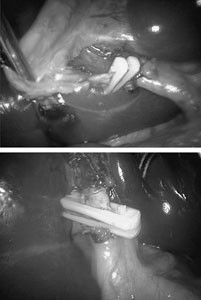

Fig. 1